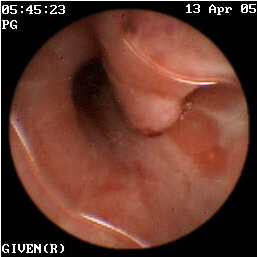

Η κάψουλα έχει επίσης ιδιαίτερη αξία στην ανεύρεση της εστίας της αιμορραγίας αγνώστου αιτιολογίας στη νόσο του Crohn (εικόνες 1,2). Οι Legnaniκαι συν του16 εκτίμησαν 11 ασθενείς με νόσο Crohnκαι αδιευκρίνιστη αιμορραγία και προσδιόρισαν την ακριβή αιτία της στους 9 από αυτούς.

1  2

Eικόνα 1. Βαριά φλεγμονή του βλεννογόνου             Εικόνα 2. Αυτόματη αιμορραγία ειλεού σε ασθενή

με σχηματισμό ψευδοπολύποδα.                             με γνωστή νόσο Crohn